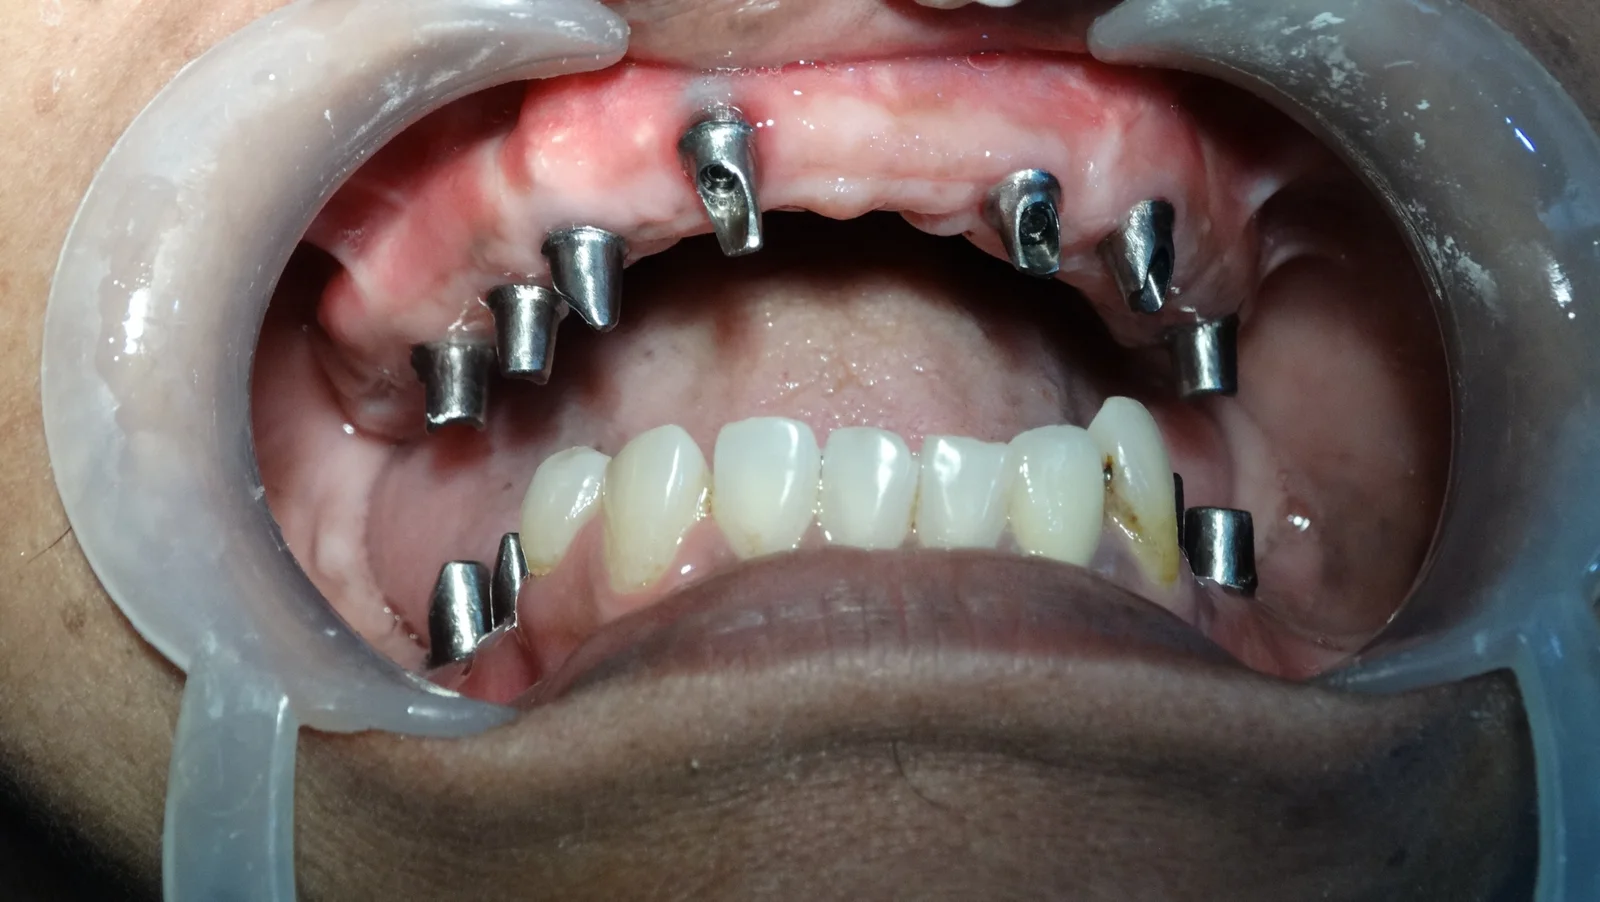

Zygomatic Clinical Cases

Prosthodontic Excellence

Elite Implantology

Zygomatic Implants

Zygomatic implants are an advanced implant technique where they are fixed to the Zygomatic arch for the upper jaw.

Eliminating the use of bone grafts, these implants allow you to get the prosthesis within 24 to 72 hours, unlike conventional implants that require months of waiting.